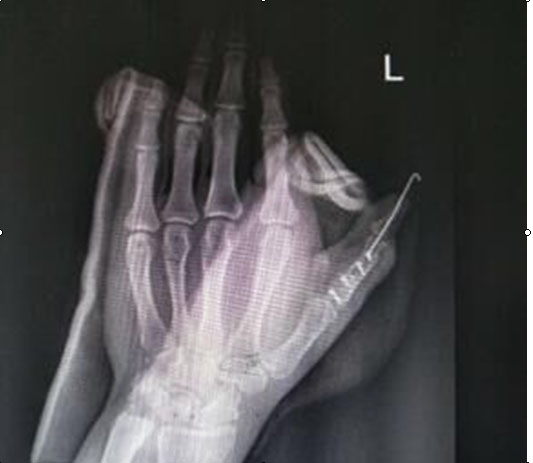

(图为手术后X光片)

我院创伤外科收治这名患者为近节型拇指多指畸形合并三节指骨型拇指多指畸形,为所有类型中最复杂的一种,需要截骨矫形,肌腱及侧副韧带重建,或肌腱移位,手术难度大,对临床医生除要求有丰富的临床经验外,还需要有精湛的手外科技术。在征得患者及家属同意后,创伤外科主任王直强带领科室团队精心策划手术方案,决定给患者实施左手拇指多指切除并功能重建术,手术顺利,术中术后出血少,患者手指功能得到最大限度恢复,解决并指畸形给病人带来的痛苦。